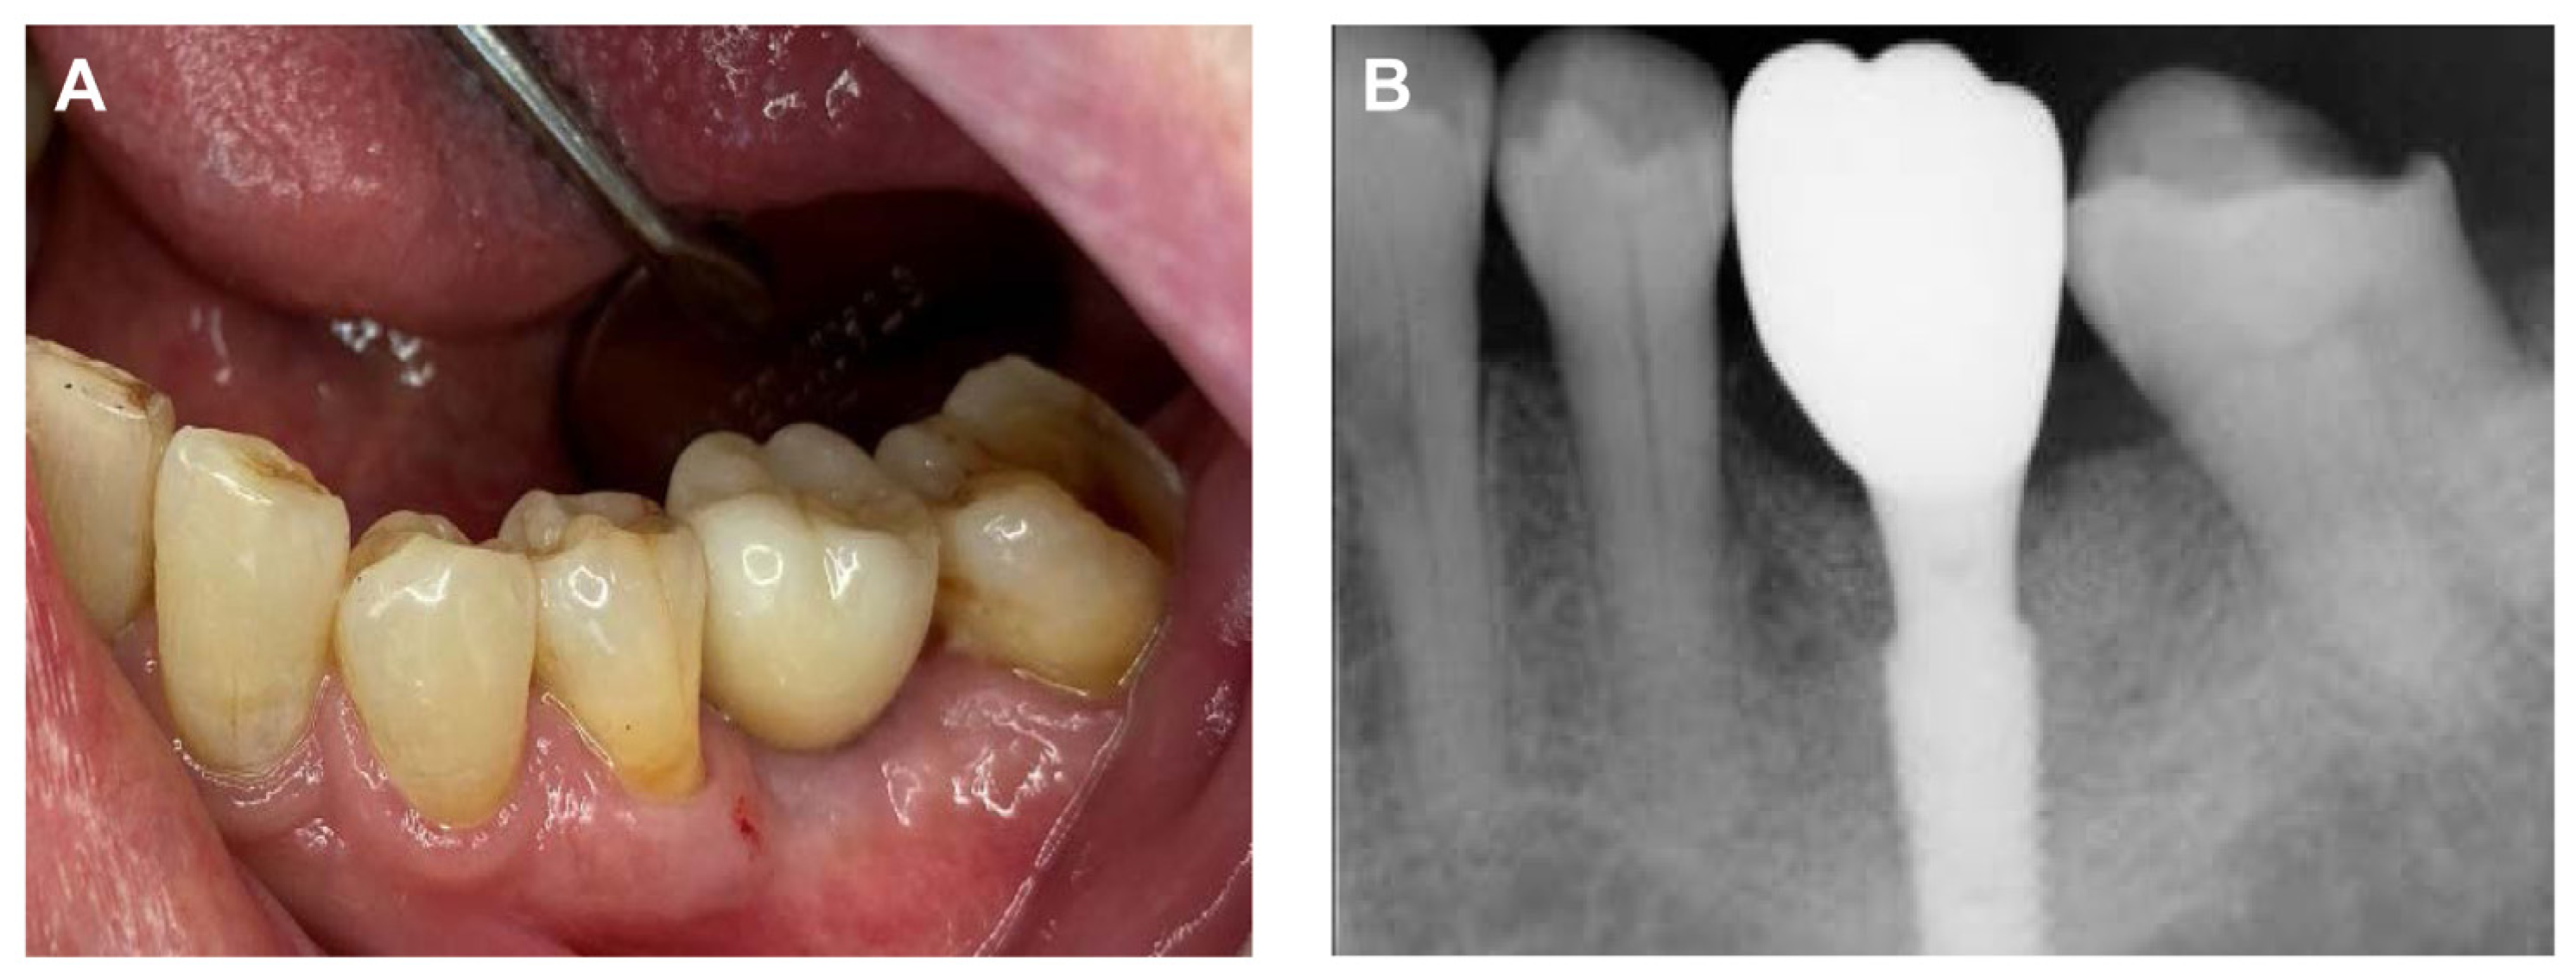

The final prosthesis was connected to the multi-abutment through the abutment screw in the oral cavity of the patient. After the intraoral adjustment, the prosthesis was connected to the implant through using an abutment screw with a torque of 25 N/cm2. The screw access hole was sealed using Teflon tape and composite resin (Gradia Direct A3, GC, Tokyo, Japan) to complete the procedure (Figure 6A), and the accuracy of the connection of the implant prosthesis was confirmed through a periapical radiograph (Figure 6B).

Figure 6. Final delivery of implant prosthesis. (A) Intraoral photograph, (B) Periapical radiograph.